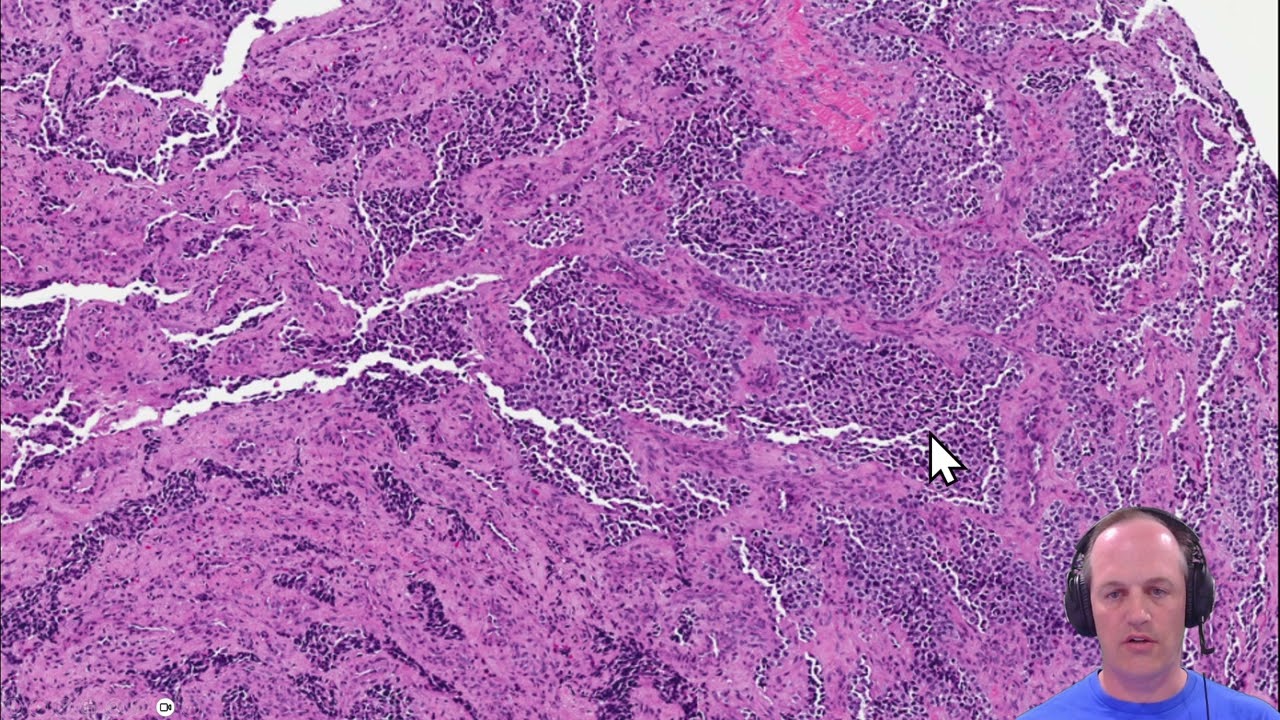

2022 07 25 Differentials for Small Round Blue Cell Tumors of the Sinonasal Tract

Small round blue cell tumors of the sinonasal tract.